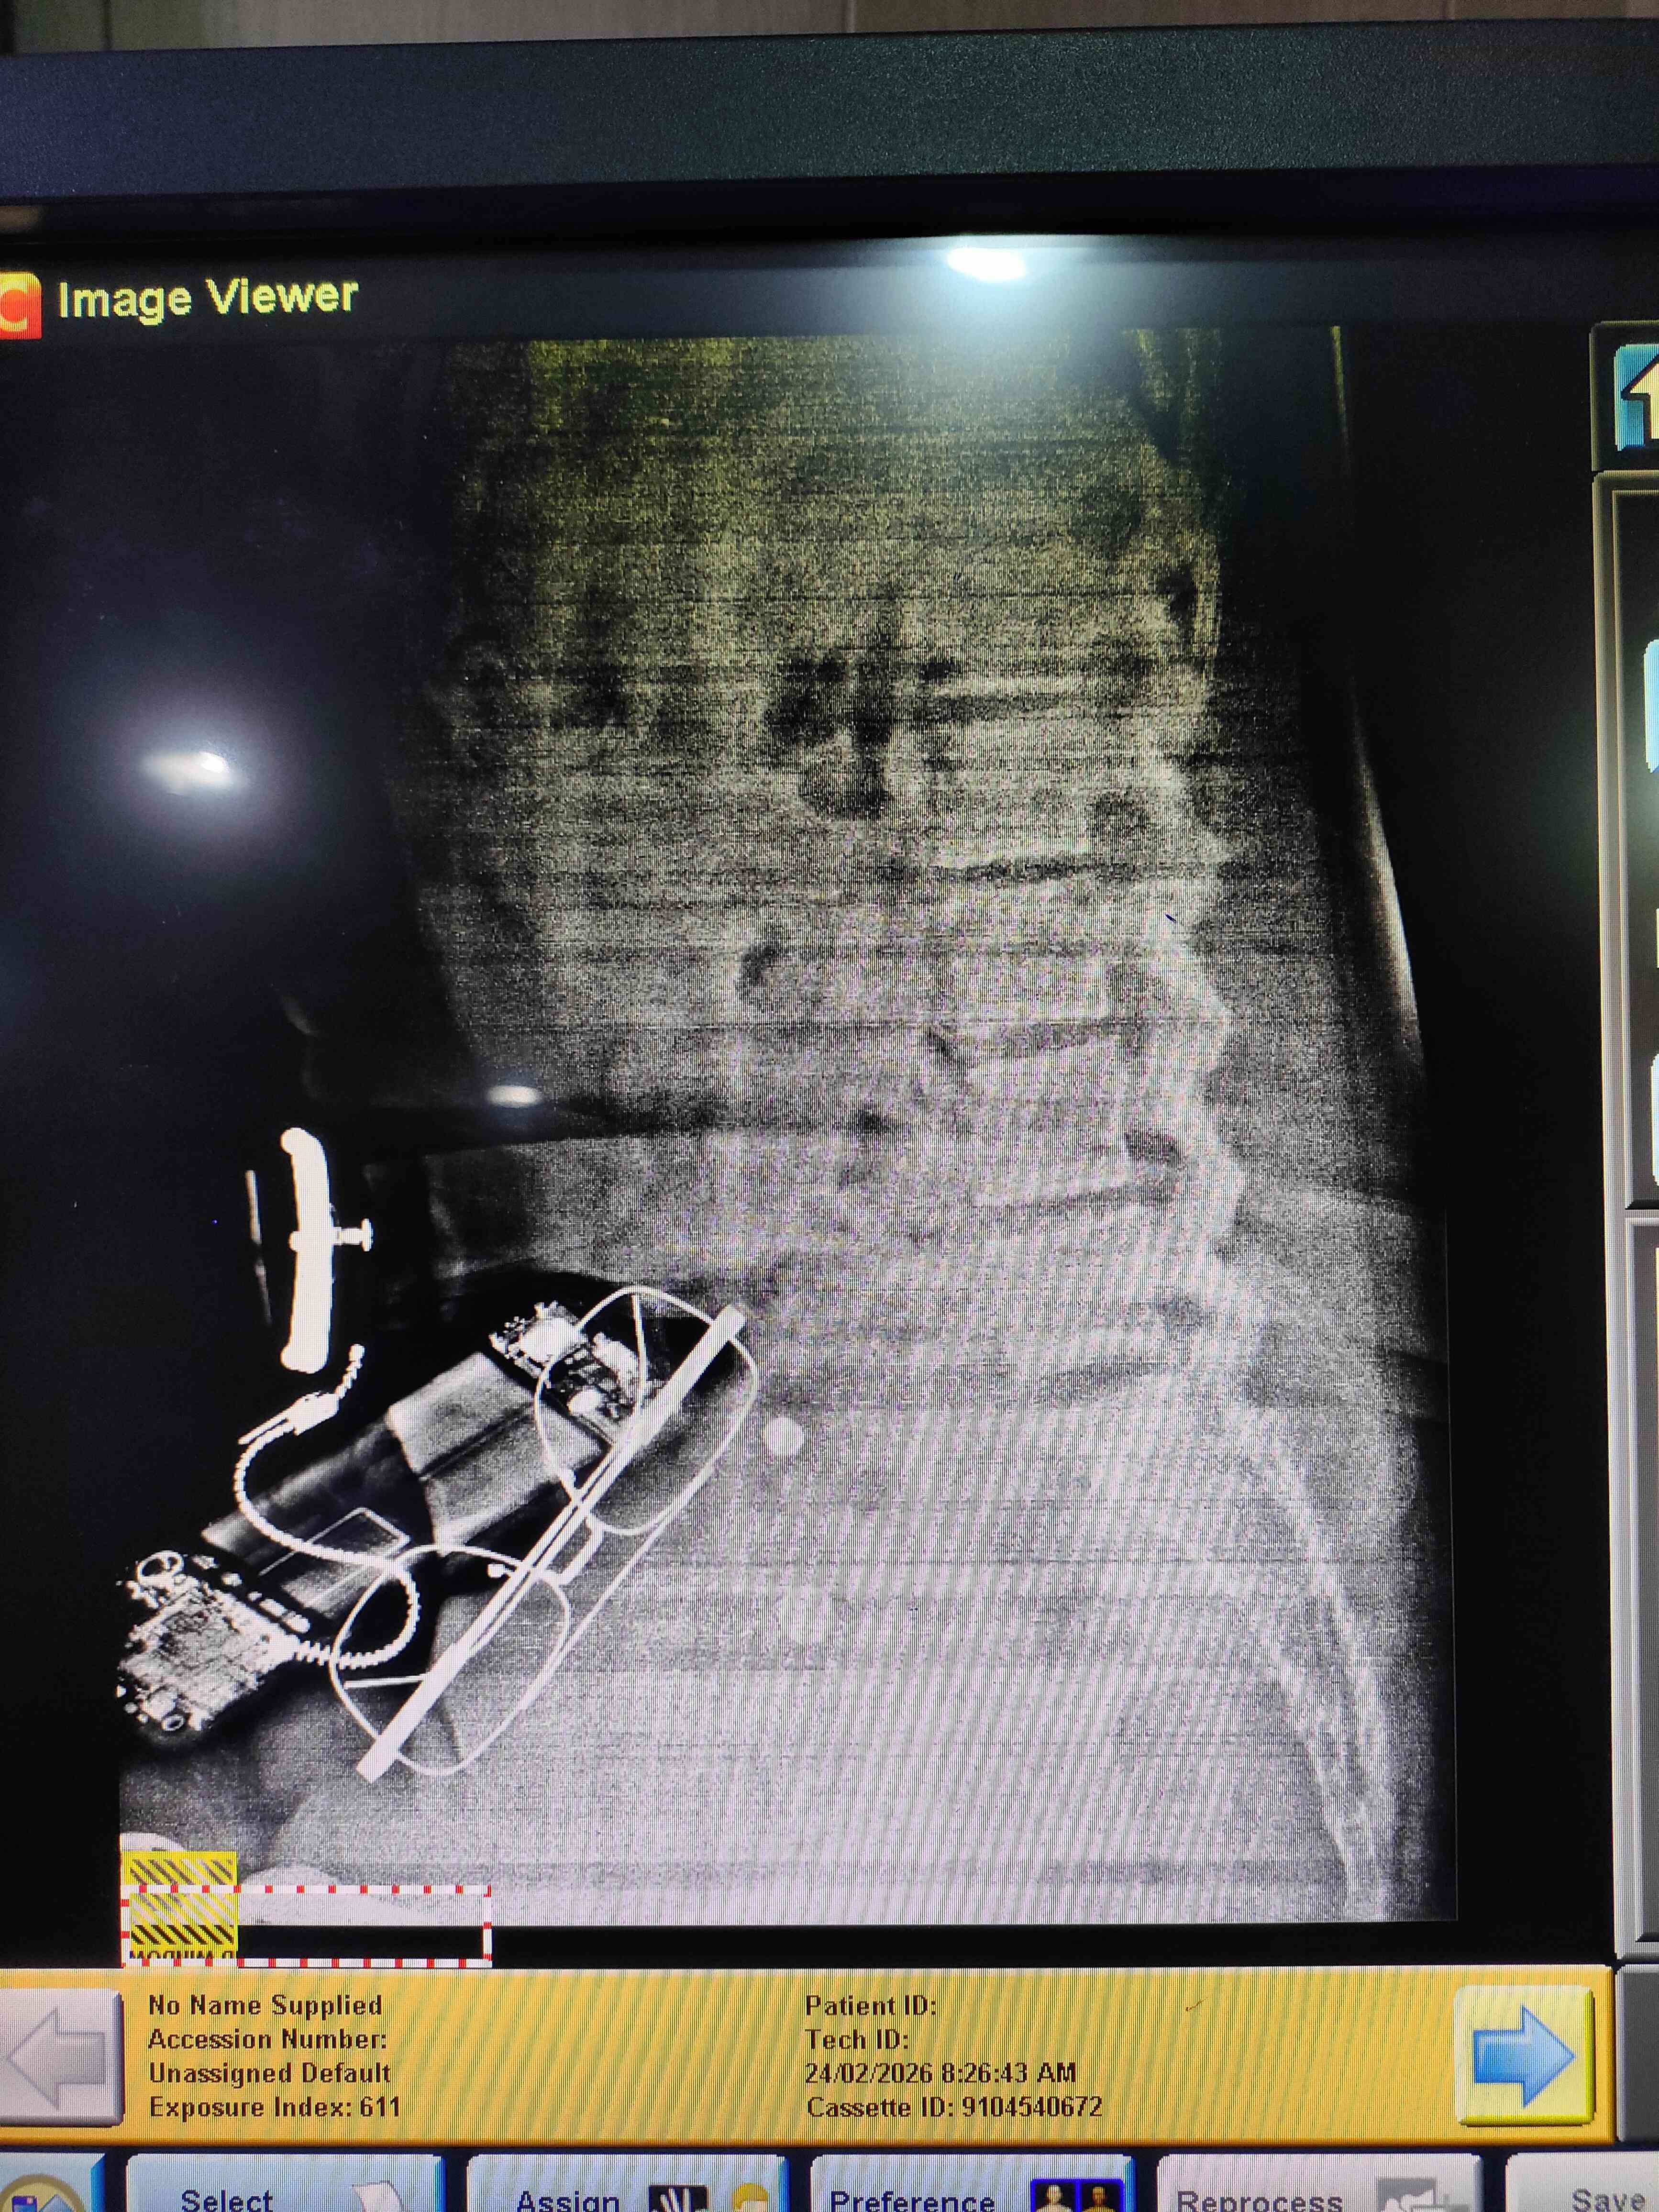

الالم اسفل الظهر تزداد قليلا عند الانحناء للامام هذه الاشعة الخاصة بي هل يوجد هناك خطورة ؟

اسباب الام الظهر كثيره ومتنوعه منها الحركي كمشاكل الغضاريف ومنها الالتهابي كامراض الروماتيزم وهي كثيره وغيرهم لذا عليك مراجعة طبيب روماتيزم للفحص السريري واجراء اللازم من تصوير وتحليل للدم وغيرهم وهذه لا تكفي للتشخيص 0 2026-03-03T08:30:34+00:00 2026-03-03T08:30:34+00:00

اسباب الام الظهر كثيره ومتنوعه منها الحركي كمشاكل الغضاريف ومنها الالتهابي كامراض الروماتيزم وهي كثيره وغيرهم لذا عليك مراجعة طبيب روماتيزم للفحص السريري واجراء اللازم من تصوير وتحليل للدم وغيرهم وهذه لا تكفي للتشخيص